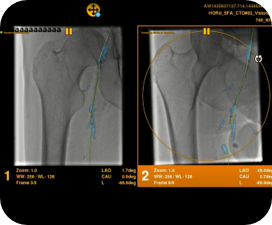

Die automatische Segmentierung von Knochen und Gefäßen und die Mittellinienverfolgung durch den Gefäßverschluss ermöglichen eine schnelle Planung anhand von präoperativen CT- oder MR-Bildern. Durch diese Kombination präoperativer CT- oder MR-Bilder mit Mittellinienverfolgung und Durchleuchtung in Echtzeit können Spezialisten außerordentlich gut sehen, wo die Rekanalisation vorgenommen werden muss und wo sich die Einstichstelle befindet, ohne die Kontrastmittelmenge erhöhen zu müssen.

Vessel ASSIST bietet eine präzise und einfache anatomische Segmentierung und genaue Gefäßquantifizierung anhand von 3D-Volumen. Zudem ermöglichen die erweiterte 3D-Roadmap und erweiterte Bildführungsfunktionen für die frontale und laterale Ebene das sichere Führen von Kathetern.